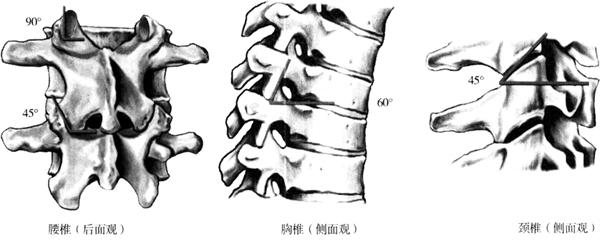

椎间关节(facet joint)(关节突间关节,zygapophyseal joint)属于滑膜关节,由上下相邻关节突的关节面构成。不同节段脊柱其椎间关节的方向也不相同。颈椎椎间关节面平坦,与水平方向成45°角;胸椎椎间关节面也平坦,与水平面成0角,与额面成20°角;腰椎椎间关节上关节面轻度凹陷,下关节面略突,与水平面成0角,与额面成45°角(图1-38、图1-39)。

图1-38 不同椎体节段关节突关节的角度及其平面展示

图1-39 椎间关节的角度

颈椎的关节面向上,约成45°倾斜,C2~C3之间的倾斜度常有变化。关节囊较为松弛,外伤时容易引起半脱位。颈椎椎间关节构成椎间孔的后壁,前与颈神经根与椎动脉邻近。上腰椎的椎间关节面近似矢状位,腰骶部则近似冠状位。椎间关节囊较松弛,借薄弱的纤维束加强。在下腰部,有坚强纤维性结构与椎弓板相连,并部分为棘间韧带所代替,前部为黄韧带。